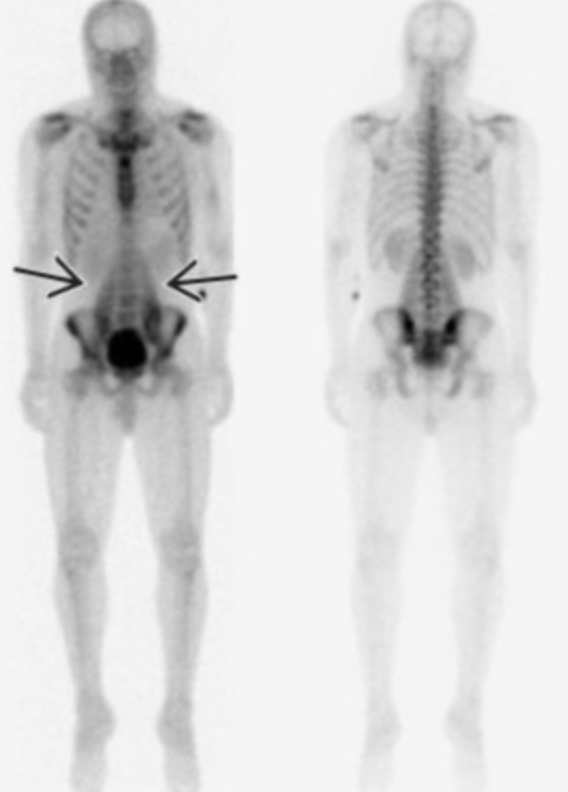

• Superscan

• Diffuse uniform tracer uptake throughout the skeleton

• Will see concurrent decreased renal activity

• Most commonly due to prostate carcinoma

• Other things looking similar if no cancer —> hyperparathyroidism

Superscan